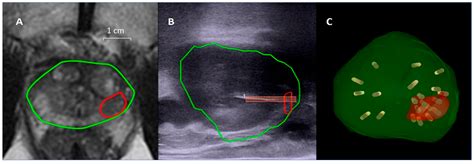

The first step is an MRI scan, which provides high-resolution images of the prostate gland. This scan helps identify any suspicious lesions or areas that may indicate the presence of cancer. The MRI images are then used to create a 3D map of the prostate, which will guide the biopsy procedure.

Fusion of MRI and Ultrasound Images

During the biopsy, the MRI images are fused with real-time ultrasound images. This fusion allows the urologist to see the suspicious areas identified on the MRI in real-time, ensuring precise targeting during the biopsy. The fusion technology enhances the accuracy of the procedure, reducing the risk of missing cancerous tissue.

The biopsy itself is performed using a transrectal ultrasound (TRUS) probe. The urologist inserts the probe into the rectum and uses the fused images to guide the biopsy needle to the targeted areas. Multiple samples are taken from the suspicious lesions and surrounding tissue to ensure a comprehensive analysis.